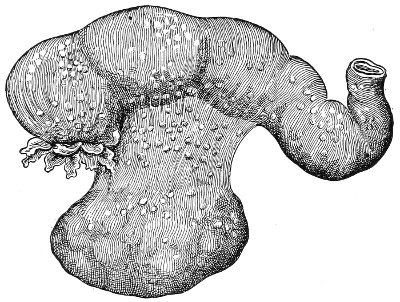

Suppuration of the vulvo-vaginal gland is accompanied by marked swelling and peripheral edema. The swelling may extend to the anus, and is of characteristic shape (Fig. 17). The pain is always severe. Fluctuation is first apparent on the inner surface of the labium majus. If the condition is not treated, one or more fistulous openings appear below the orifice of the duct, and the pus is discharged. The condition then becomes chronic. The fistulous openings persist. Acute inflammation disappears from the gland, leaving it in a condition of hypertrophic induration. A thin, milky or greenish, purulent fluid may be pressed out of the duct or the fistulous openings. Infection from this discharge may be communicated to man, or may ascend the genital 40 tract, producing inflammation of the endometrium or of the Fallopian tubes.

Fig. 17.—Abscess of right vulvo-vaginal gland.

In abscess of the vulvo-vaginal gland a free incision should immediately be made into the labium at the junction of the skin and the mucous membrane. The interior should be wiped out with pure carbolic acid and the cavity packed with gauze. If the disease is first seen in the chronic stage, after the abscess has evacuated itself, the only method of cure is to excise, with curved scissors, the whole of the indurated gland, the duct, and the fistulous tracts. The wound may be left open and packed, or it may be closed immediately with buried catgut sutures.